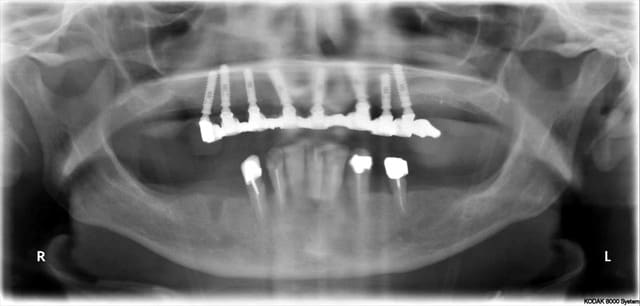

Pour ceux qui veulent voir l’OTP du cas de béotien.